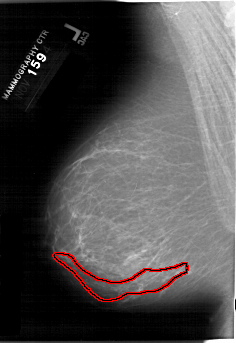

A_1202_1.LEFT_MLO

FILE: A_1202_1.LEFT_MLO.OVERLAY

TOTAL_ABNORMALITIES 1

ABNORMALITY 1

LESION_TYPE CALCIFICATION TYPE PLEOMORPHIC DISTRIBUTION SEGMENTAL

ASSESSMENT 5

SUBTLETY 3

PATHOLOGY MALIGNANT

TOTAL_OUTLINES 1

BOUNDARY